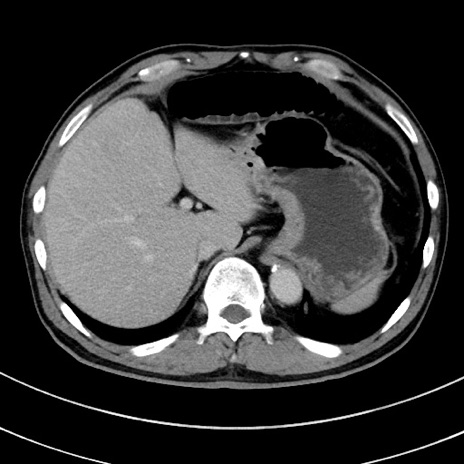

症例8(横断像)

【症例】 60歳代男性

【主訴】 黒色吐物

【現病歴】 4日前から嘔気自覚、2日前の朝食後にも嘔気あり、自分で手で嘔吐反射起こし嘔吐したところ血が混ざっていたため受診。

【既往歴】 5年前汎発性腹膜炎を伴う急性虫垂炎で手術、高血圧、前立腺肥大症、高脂血症

【身体所見】 腹部正中に手術癩痕あり 腹部平坦・軟圧痛なし膨満感あり

【データ】WBC 8400、CRP 4.54